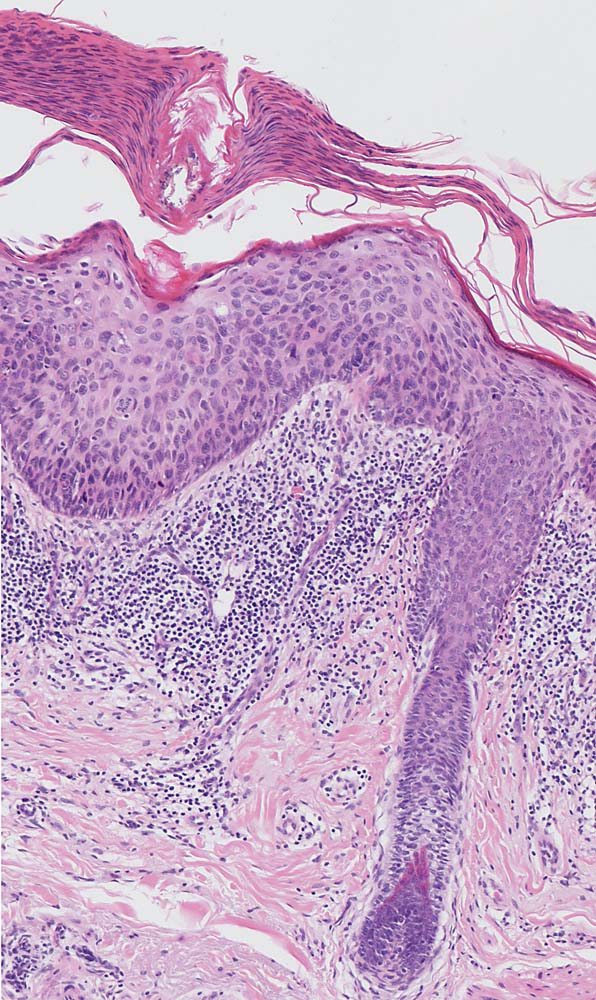

Morphologie:

Die Epidermis zeigt obligat dysplastische Veränderungen. Die Dysplasie kann sich auf das untereste Epitheldrittel beschränken (leichte Dysplasie) oder die gesamte Epithelbreite betreffen (=bowenoide aktinische Keratose bzw. Carcinoma in situ). In der Dermis findet sich als Zeichen der chronischen UV Schädigung der Haut immer eine ausgeprägte solare Elastose. Das histologische Bild ist abgesehen von diesen zwei obligaten Befunden sehr variabel. Dyskeratotische Zellen und Mitosen finden sich häufig. Charakteristisch ist auch das Vorliegen einer alternierenden Para- und Orthokeratose, die unterschiedlich stark ausgeprägt ist. Manchmal findet man eine Atrophie der Epidermis mit schmalem Stratum corneum oder umgekehrt eine massive Hyperkeratose wie beim Cornu cutaneum. Akrosyringium und innere Abschnitte der Haarfollikel sind von den dysplastischen Veränderungen ausgespart. Die Epidermis zeigt häufig eine unregelmäßige Hyperplasie mit in das Stratum papillare reichenden Knospen. Bei Ausdehnung der Dysplasie entlang von Haarfollikeln in die Tiefe, können sich bei zu oberflächlicher Abtragung der Läsion Lokalredzidive ausbilden.

Unterschieden werden mehrere histologische Subtypen der aktinischen Keratose: hypertropher, atropher, bowenoider, akantholytischer und pigmentierter Typ. Beim gleichen Patienten können unterschiedliche Subtypen vorkommen.